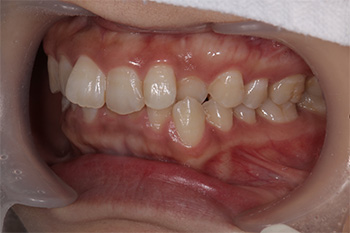

Before

After

| 治療の内容 | マウスピース型矯正装置(インビザラインGo)による部分矯正とホームホワイトニングの治療 |

|---|---|

| 期間・回数 | 10ヶ月・9回(カウンセリング・検査含む) |

| 費用 | 自由診療:マウスピース型矯正装置(部分矯正)+ホームホワイトニング 総額 400,000円(税込 440,000円) |

| リスク・副作用 |

|